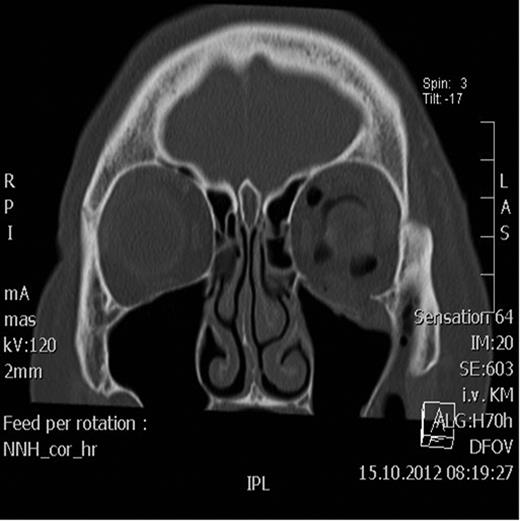

Spiral computed tomography (CT) was performed using 1 mm slices with a soft tissue and bone algorithm. A non-dislocated orbital floor fracture and a large amount of intraorbital emphysema were found, especially retrobulbar between the ocular muscles and around the optic nerve, causing exophthalmos (the distance from the corneal apex to the line connecting orbital rims was 18.8 mm; normal 9.0 mm) (Figs 1–2).

Coronal CT scan showing the retrobulbar emphysema prior to decompression.